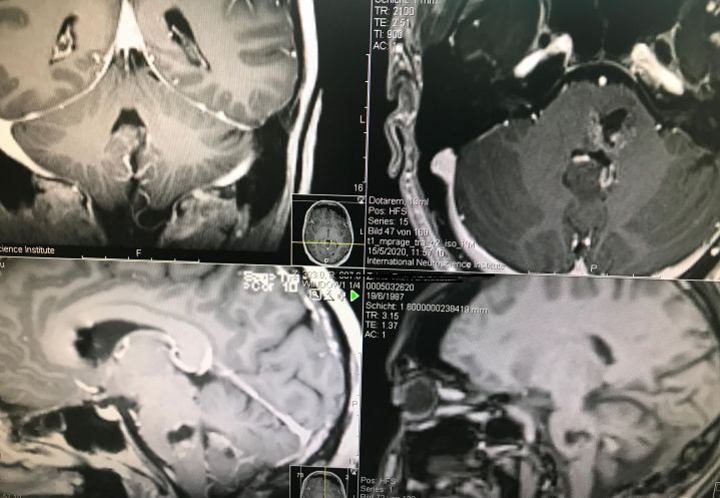

巴特朗菲教授指導手術(shù)的8個病例的術(shù)前磁共振資料,每個手術(shù)難度都不低。